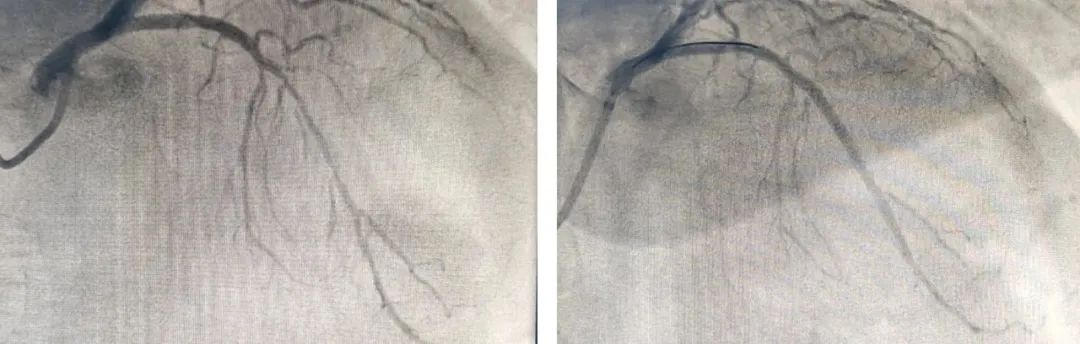

造影结果提示前降支及右冠病变,阿公的前降支近段完全闭塞病变,于前降支植入支架一枚,通过开通狭窄或闭塞的冠状动脉,从而达到解除狭窄,改善心肌血供的目的。术后,患者的血压及症状都得到明显改善。

▲介入治疗术前(左)、术后(右)影像对比(例)